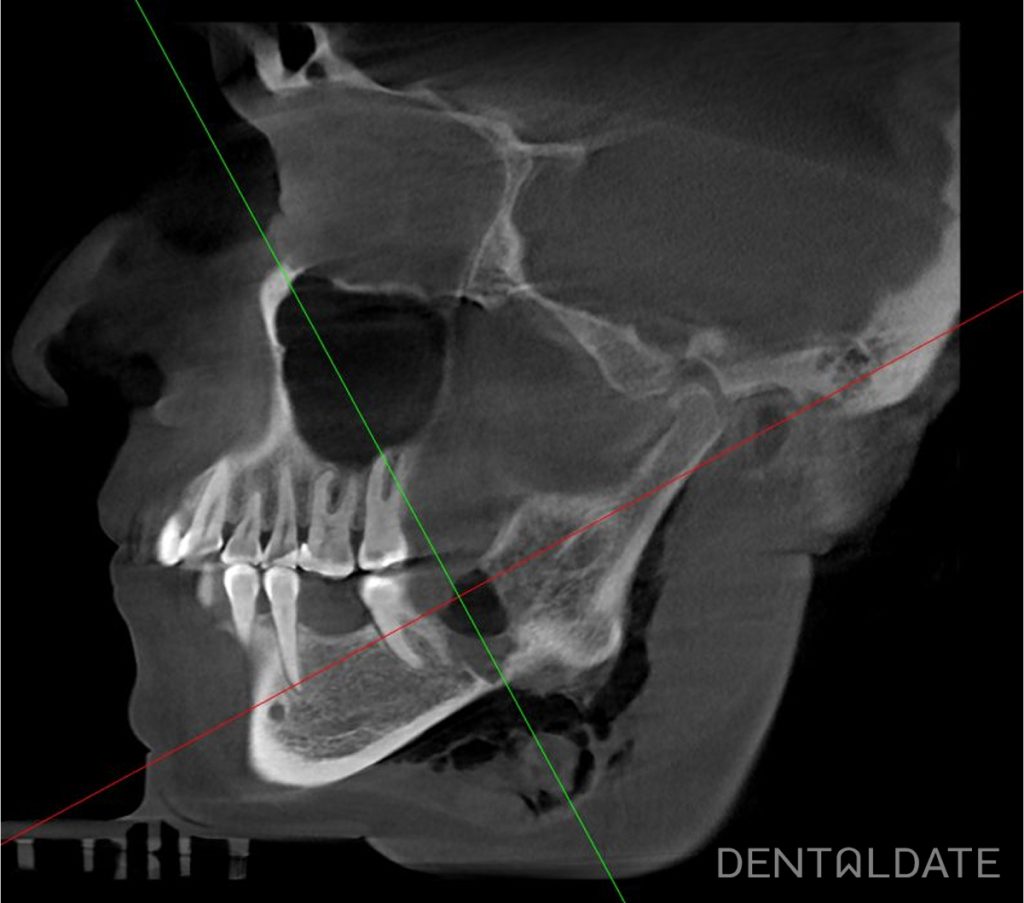

CBCT: the axis of the tooth 4.8 is tilted towards the neighboring tooth 4.7, the tooth has three roots, one of which is mace-shaped, the other has a bend of 90 degrees. The roots are located in the immediate vicinity of the mandibular nerve.